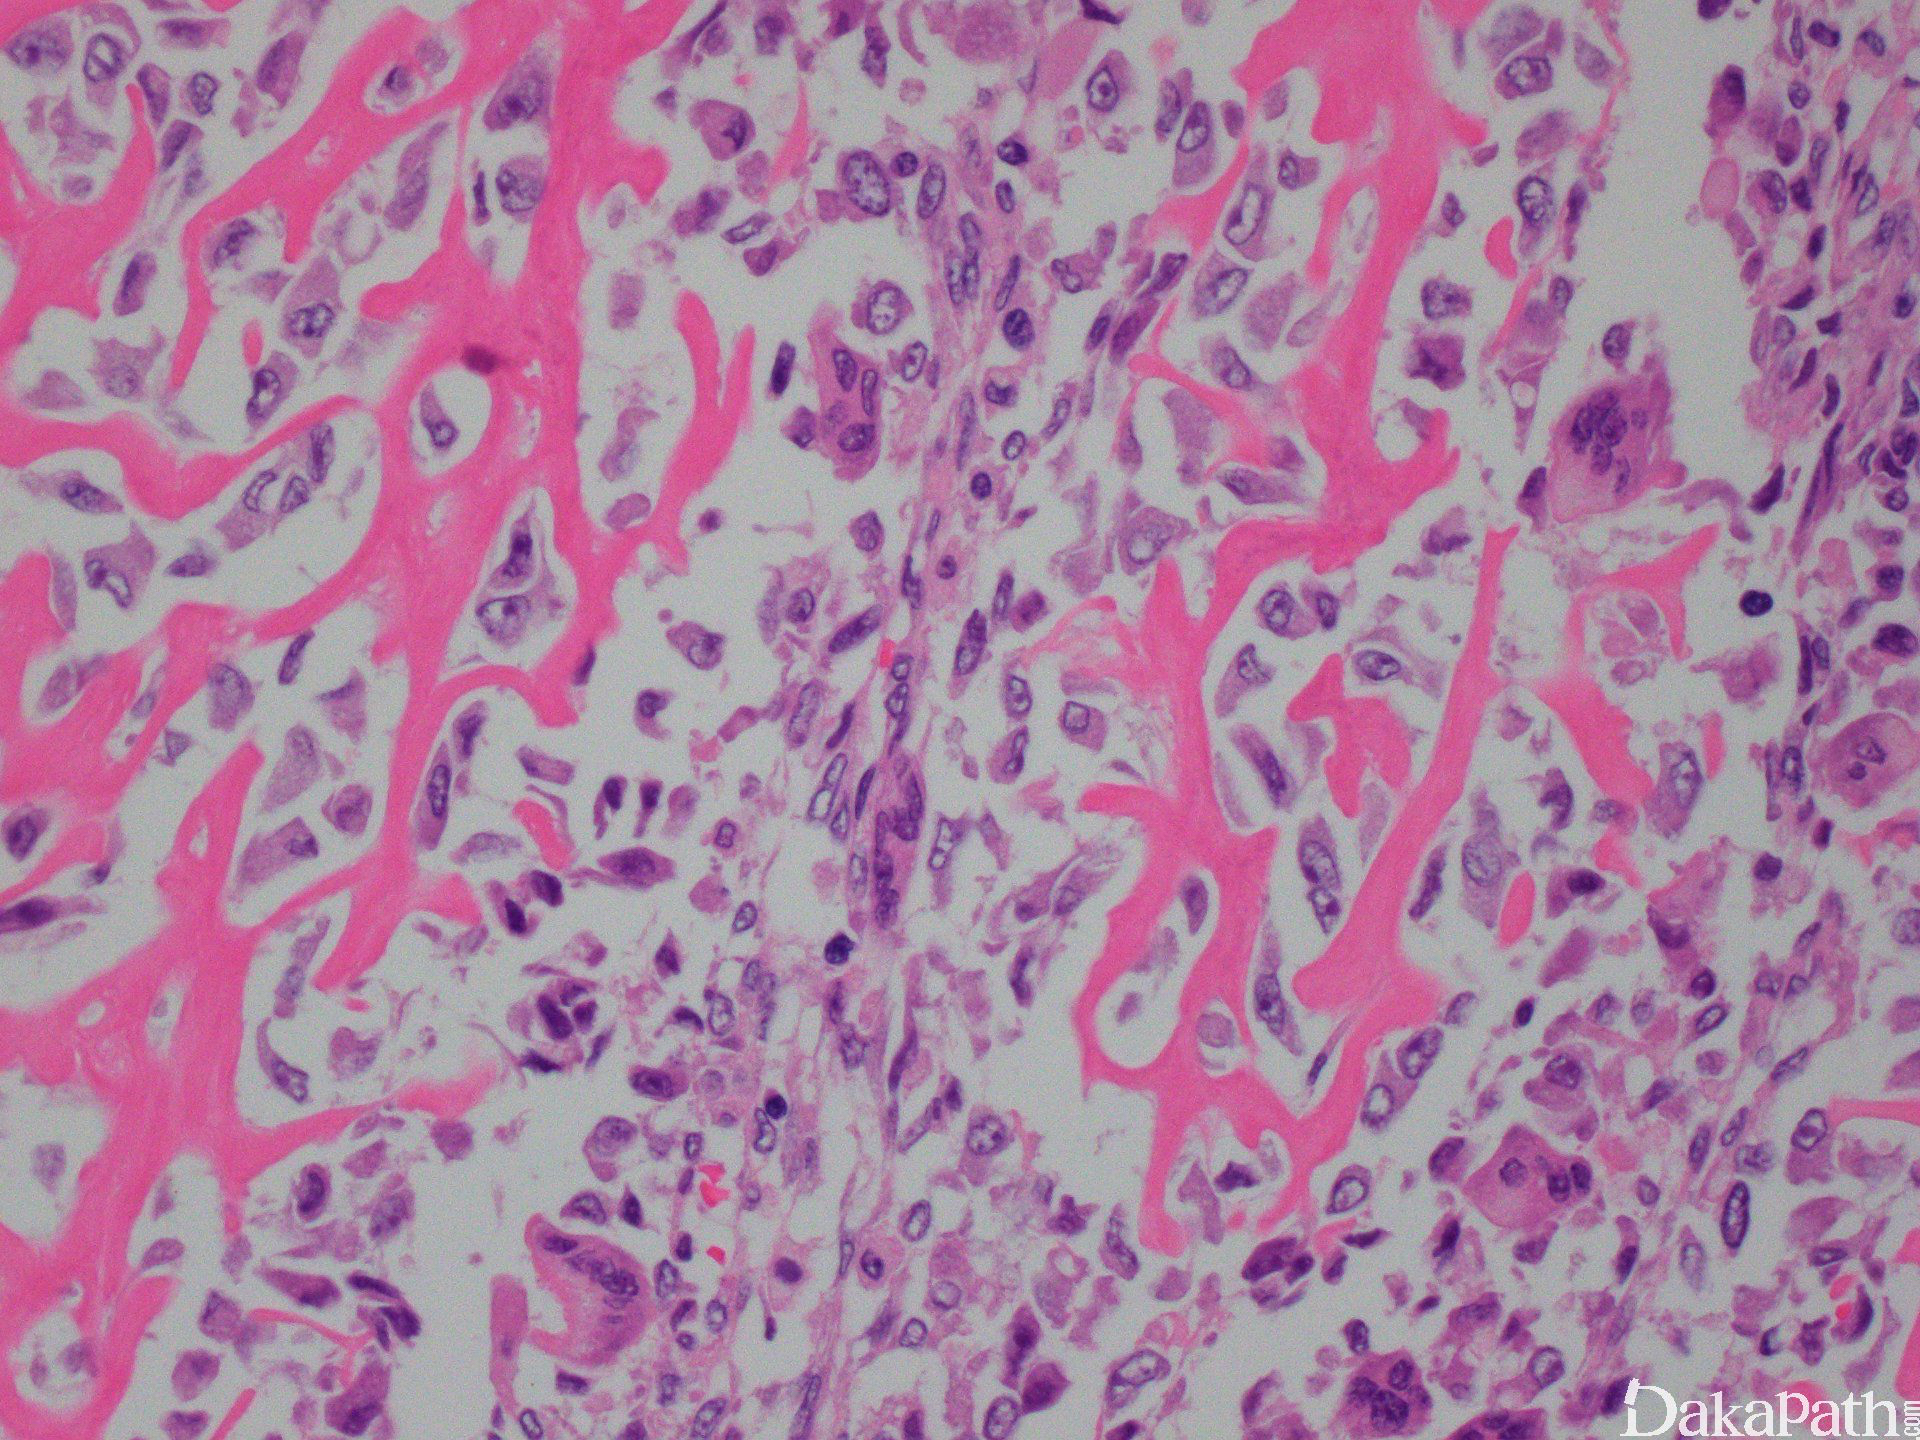

组织上高级别肉瘤可见上皮样、浆细胞样、纺锤形、卵圆形及小圆形细胞、透明细胞、单核或多核巨细胞或梭形细胞,肿瘤可直接产生骨基质,位于中心或偏心性深染的胞核,核仁显著,核分裂活跃伴不典型核分裂,不定量的嗜酸性胞浆。

肿瘤细胞与肿瘤性骨表面密切相关,被基质包绕后的肿瘤细胞不典型性减轻,体积变小,大量钙化时肿瘤细胞缺乏不典型性,该过程称为“正常化”。

肿瘤性骨多少不等,呈编织状结构,可见原始、杂乱小梁呈粗糙蕾丝样或片状融合的小梁。肿瘤性层状骨非常罕见。骨呈嗜酸性或嗜碱性及杂乱沉积的黏合线(类似 paget 样外观)。